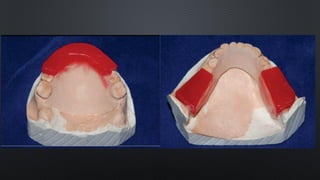

FORMATO DOS ARCOS

RELAÇÃO INTERDENTAL

RELAÇÃO ENTRE OS ARCOS

RELAÇÃO DENTÁRIA INTRA-

ARCO

REABILITAÇÕES PROTÉTICAS

ORTODONTIA

TRATAMENTO DAS DTM`S